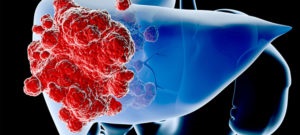

- cancer la ficat;

Cu varsta, copilul are un risc crescut de a dezvolta cancer la ficat si ciroza. nou-născuții prematuri consecințe icter va fi mai severă. La sugari care au fost recuperați de hepatită, complicații pot apărea pe tot parcursul vieții. Acest lucru poate fi redusă imunitate, ficat sărac.